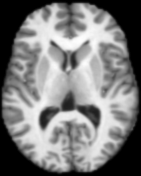

5 Application to Brain MR Images

An important building block for the analysis of brain MRI populations is the definition of a metric that measures how different two brain MRI are. A mathematically well motivated and popular approach for distance computations between brain images is based on large deformation diffeomorphic metric mappings (LDDMM (Miller et al., 2002)). Here we explore optimal transport distance as an alternative metric for comparing brain images.

To solve for the optimal transport map between two 3D brain images we extract for each image a point cloud from the intensity volumes. Each point represents a voxel as a point in 3-dimensional space, the location of the voxel. The mass of the point is equal to the intensity value of the voxel, normalized to sum to one over all points. For illustration, Figure 9 shows a single slice extracted from the original volumes and optimal transport maps between the two slices. This 2D problem resulted in point set of approximately points.

|

|

| (a) | (b) |

|

|

| (c) | (d) |